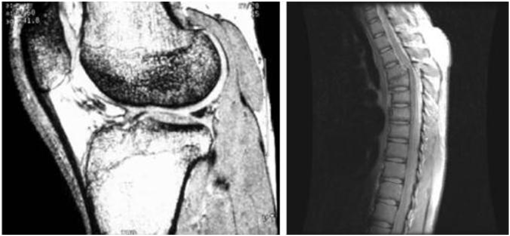

• 주요 응용분야: 의학(MRI: magnetic resonance image), 천문학

Image

인체의 MRI 무릎, 척추